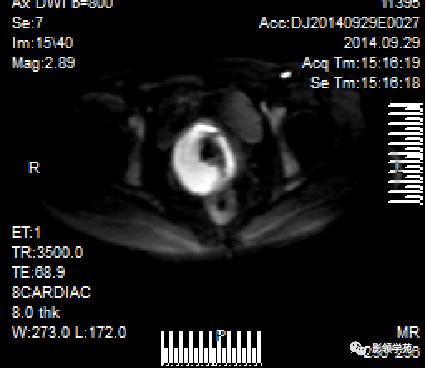

磁共振扩散加权成像,DWI

DWI是目前唯一能在活体观察组织水分子微观运动的无创性影像学方法,可以检测出与组织含水量变化相关的形态学和生理学早期改变,并以表观扩散系数(ADC)值来量化表示。

DWI:局限性高信号,癌组织ADC值<癌旁组织<小于正常宫颈组织